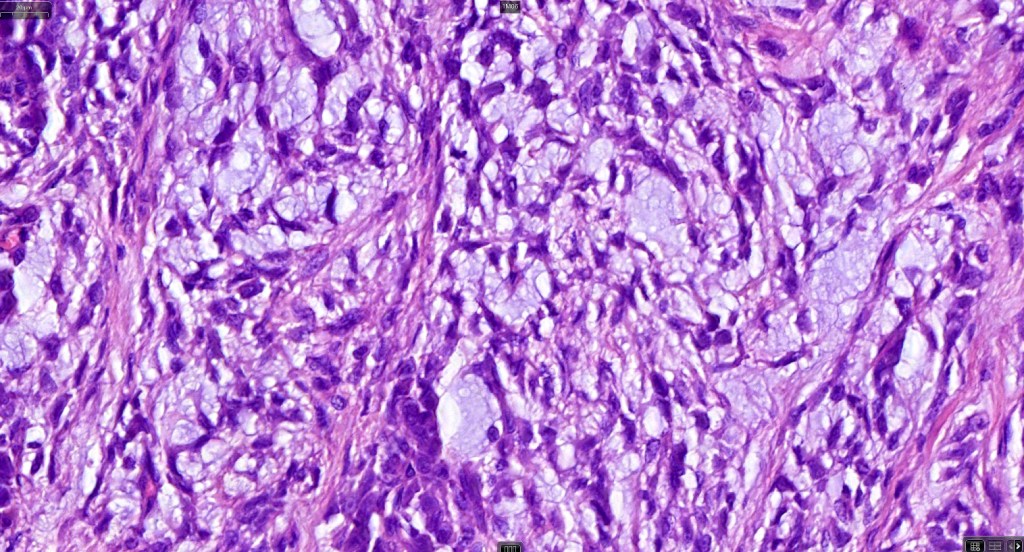

•Pure population of myoepithelial cells dispersed in sheet-like, reticular, whorled or fascicular patterns in a myxoid or hyaline stroma

•Cell types include epithelioid, spindled, histiocytoid & plasmacytoid

•Oncocytic & clear cell sometimes present

•Syncytial myoepithelioma characterized by sheet-like growth of ovoid to spindle cells with pale cytoplasm, syncytial borders & vesicular nuclei